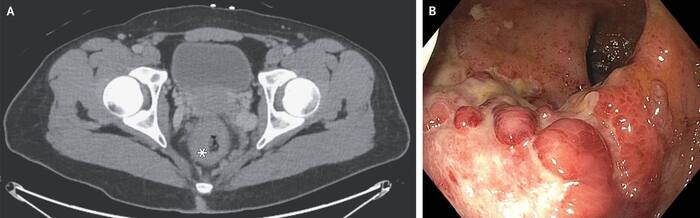

26-летний мужчина обратился в отделение неотложной помощи с 1-недельной историей лихорадки и кровавого стула. У него был восприимчивый анальный секс без презерватива с новым партнером-мужчиной за 3 недели до обращения. При физическом осмотре был небольшой внешний геморрой, но без боли в животе, поражений половых органов или паховой лимфаденопатии. Компьютерная томография таза показала утолщение стенки прямой кишки (фото А, звездочка) и периректальную лимфаденопатию — результаты, которые указывают на инфекционный проктит, воспалительное заболевание кишечника или рак прямой кишки. Последующая гибкая сигмоидоскопия показала узелковую слизистую оболочку с эритемой и язвой в дистальном отделе прямой кишки (фото B).

Биопсия была отрицательной на рак. Тест на амплификацию нуклеиновой кислоты для Chlamydia trachomatis, который был проведен на ректальном мазке. Был установлен диагноз хламидиозного проктита. Тестирование на другие инфекции, передающиеся половым путем, выявило положительный результат на вирус иммунодефицита человека с количеством клеток CD4 551 на кубический миллиметр (справочный диапазон, от 560 до 1840) и вирусной нагрузкой 129 000 копий на миллилитр (нижний предел обнаружения, 20). Начато лечение доксициклином и антиретровирусными препаратами. Через пять дней симптомы были купированы.